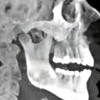

Рентгенография ВНЧС

Рентген височно-нижнечелюстного сустава. Метод неинвазивного исследования височно-нижнечелюстного сустава, основанный на способности тканей ослаблять рентгеновские лучи и фиксировать степень ослабления путем получения черно-белых изображений. Визуализируйте суставную область, внутреннюю структуру и расположение составляющих ее костей, точку суставного сустава. Методика применяется при диагностике переломов и смещений суставных поверхностей. Он также используется для определения плотности кости и патологических образований как внутри костей, так и в суставе и вокруг него. Назван для выявления инфекционно-воспалительных процессов. Экзамен проводится в амбулаторных условиях, не требуется никакой специальной подготовки. По показаниям проводится одновременно рентгенография височной кости и нижней челюсти.